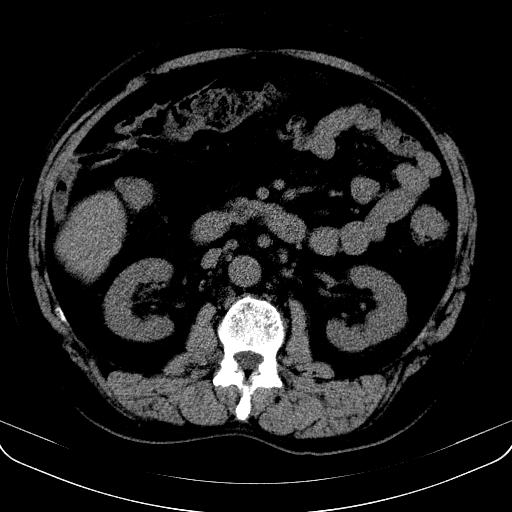

以下是引用jia119在2008-3-5 13:31:00的发言:[br]肝内多发片状低密度影,密度不均,我还是考虑肝ca可能,另肝内小囊肿,胆囊增大。

以下是引用形影不离在2008-3-5 12:18:00的发言:[br]肝硬化伴门脉高压征,肝内占位待排,增强再说.

以下是引用随光逐影在2008-3-5 21:11:00的发言:[br]肝硬化伴门脉高压(食管下段静脉曲张),肝癌不排除。建议:行ct增强扫描检查。

以下是引用同在2008-3-5 13:56:00的发言:[br]考虑肝癌可能性大,胆囊增大.